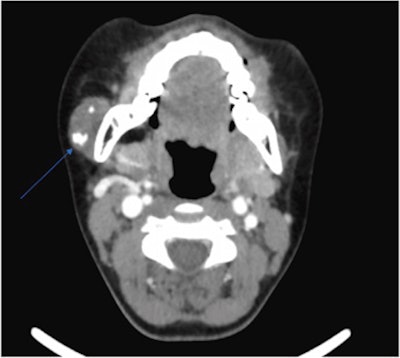

Attempts to conduct an ultrasound-guided biopsy failed because the needle wouldn't penetrate the lesion. Therefore, the patient underwent computed tomography (CT) and magnetic resonance imaging (MRI) of her neck, which showed an unusual lesion with calcification that appeared toothlike near the border of the girl's parotid gland and masseter muscle, the authors wrote.

An axial CT with contrast image reveals a lesion in the 12-year-old's right parotid gland of intermediate density containing internal foci of calcification. Images courtesy of Garry et al. Licensed by CC BY 4.0.